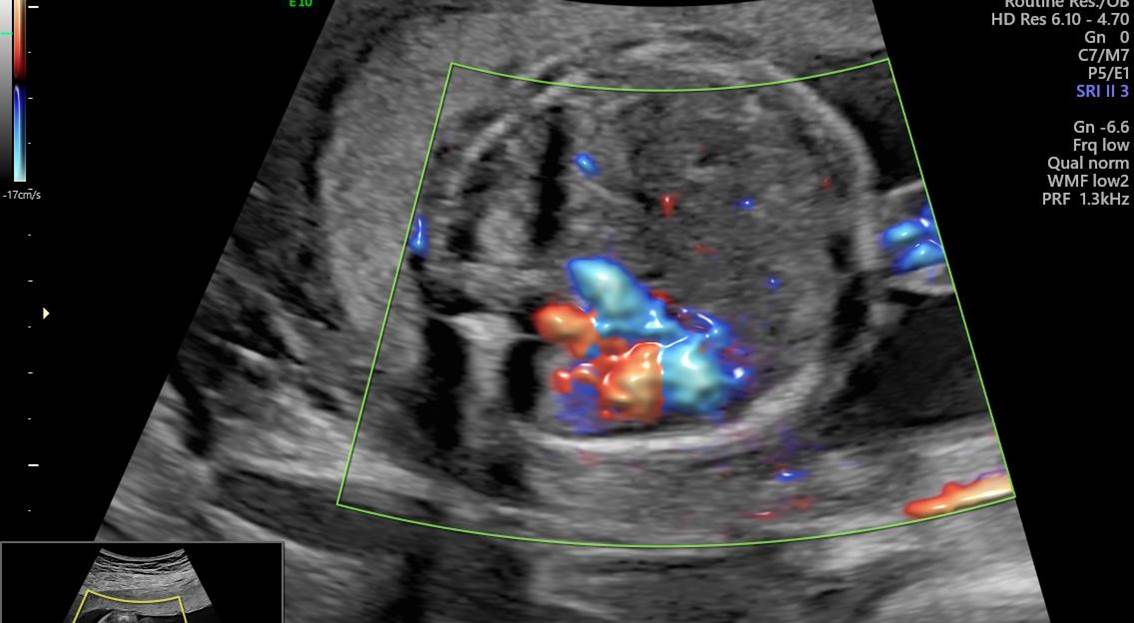

Вопрос 3

Оцените видеоклип брюшной полости плода в 23 недели беременности, установите диагноз и дальнейшую тактику ведения беременности